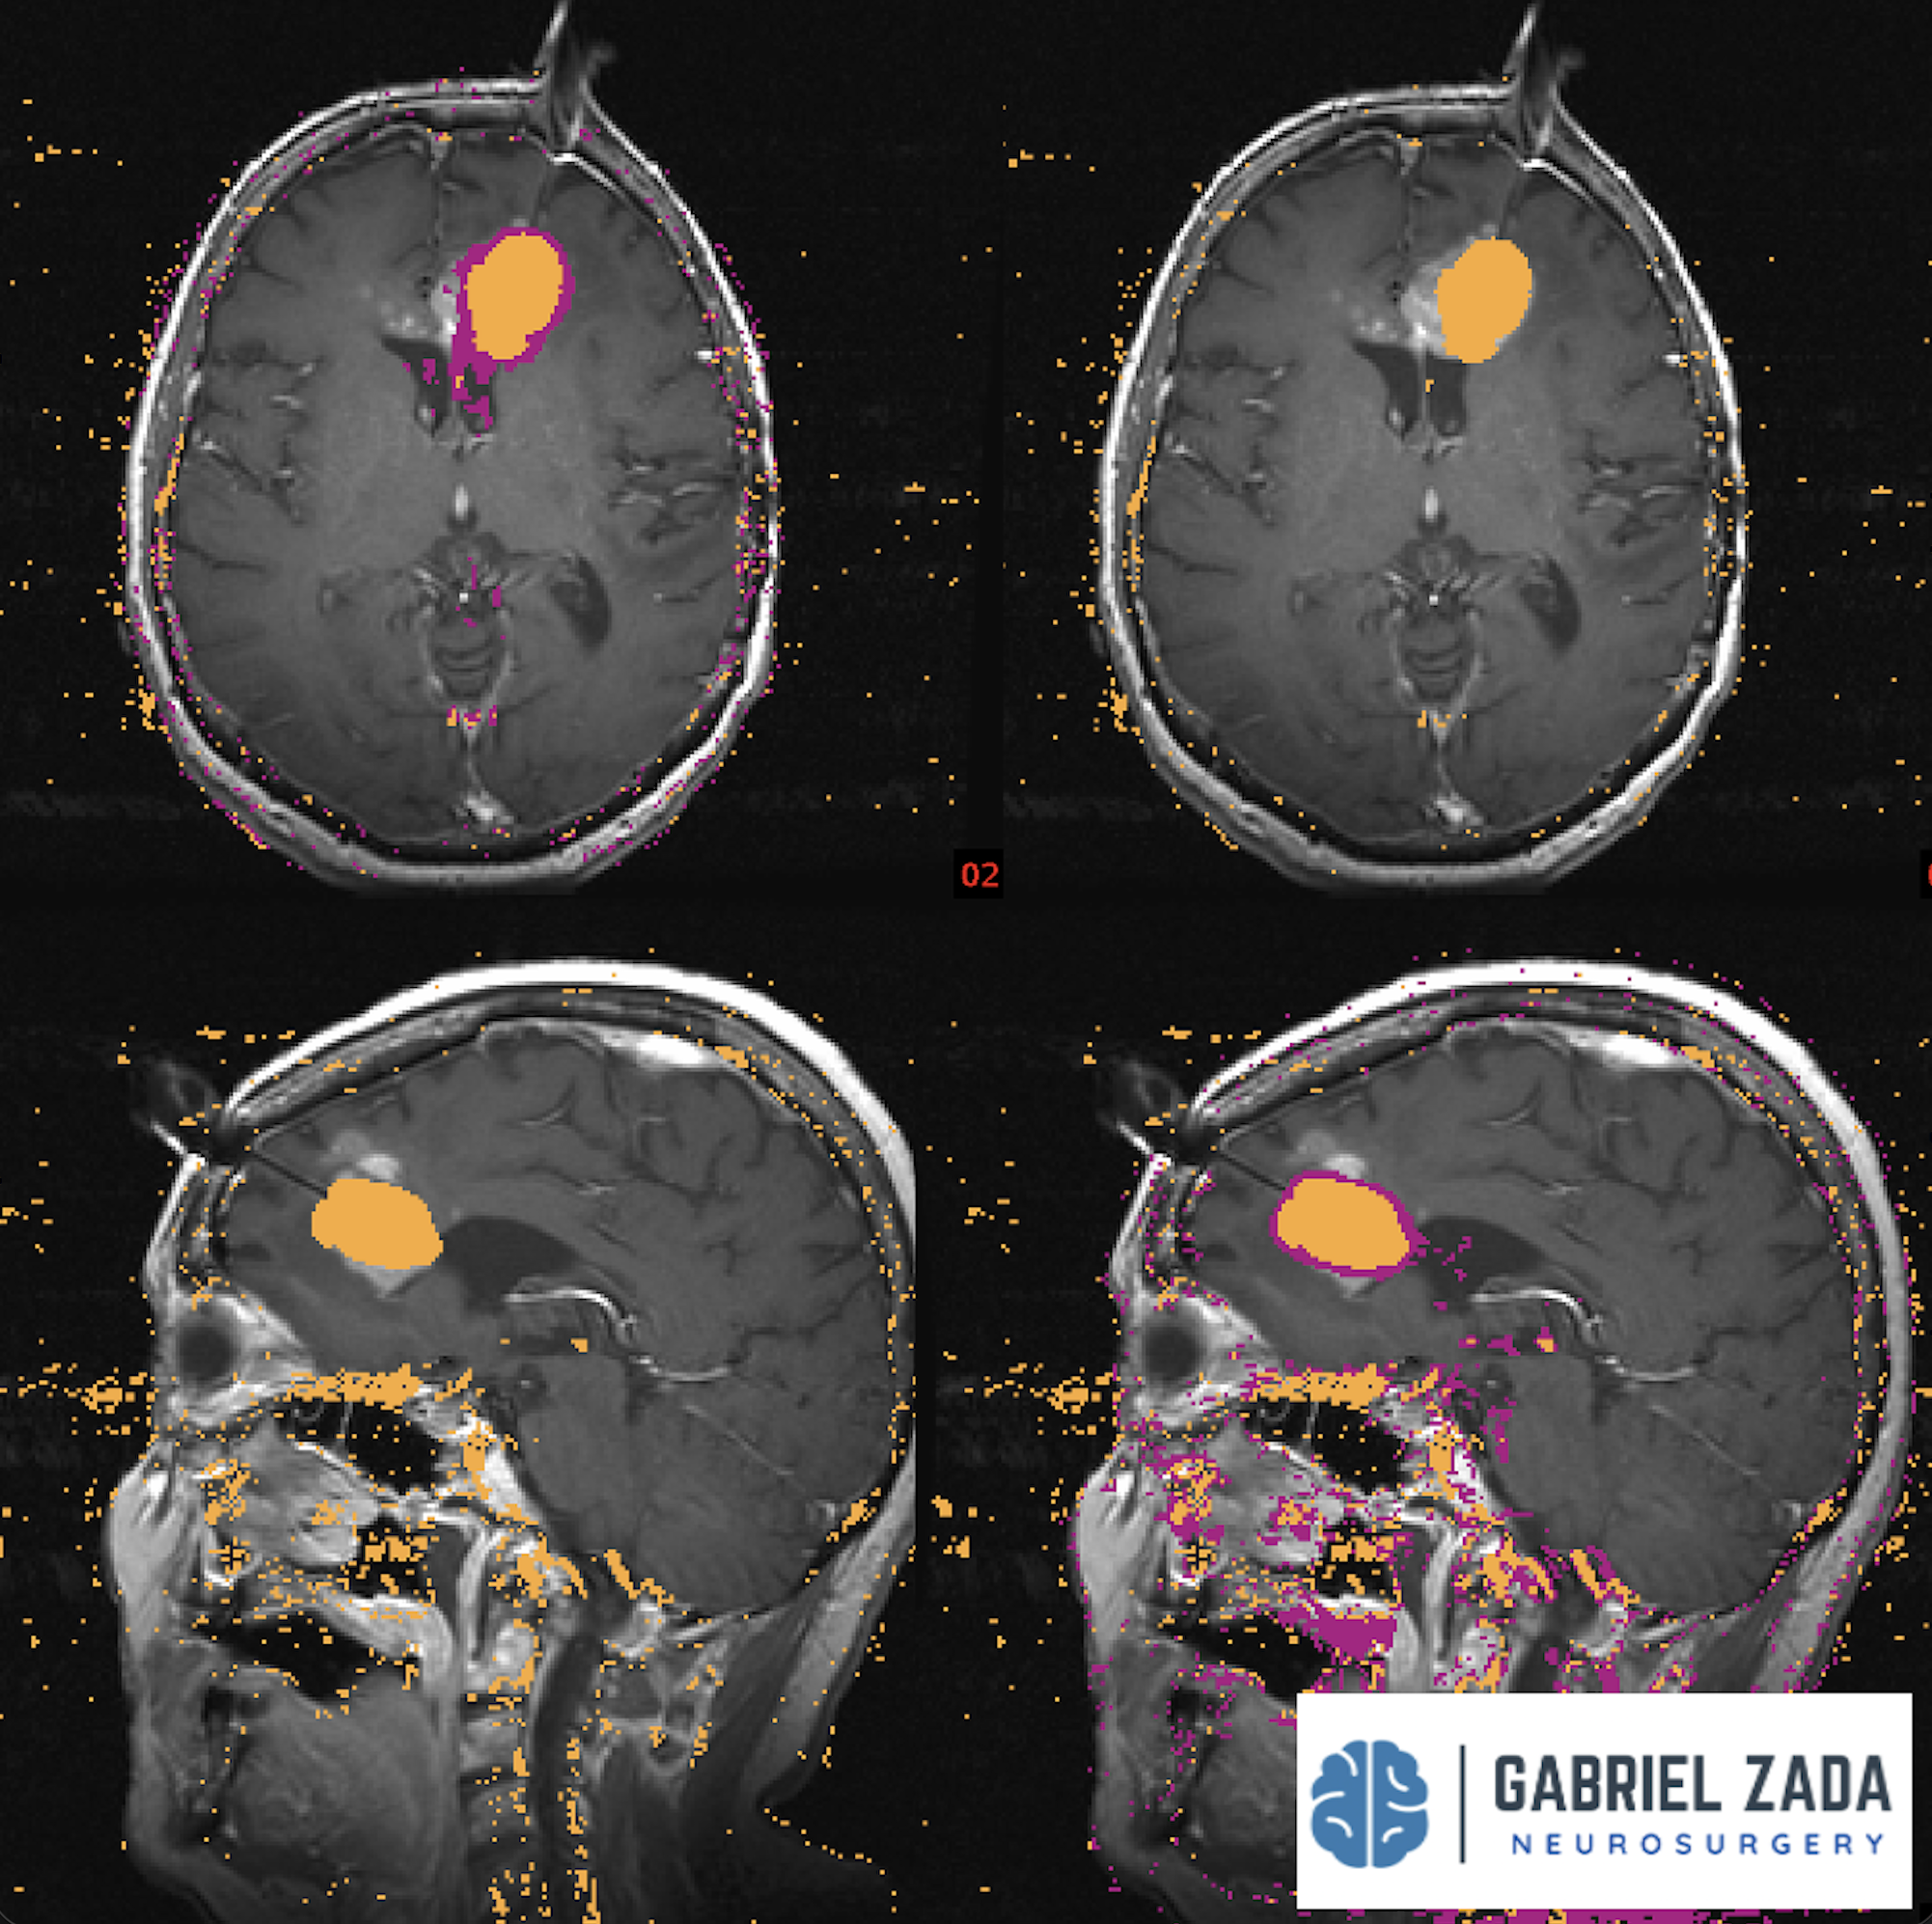

Explore this comprehensive gallery featuring pre‑ and post‑operative imaging of patients with skull‑base tumors treated by Gabriel Zada, MD, MS, FAANS, FACS. These cases highlight Dr. Zada’s expertise in advanced neurosurgical techniques and outcomes.

*Representative cases shown for educational purposes. All images de-identified. Individual results vary.